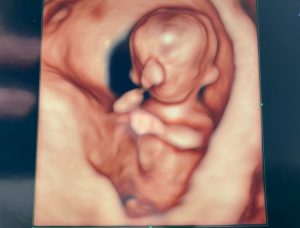

今回(妊娠5ヵ月:16w2d)のエコー写真

人間らしくなってました!

顔立ちもはっきりしてきて可愛い♡